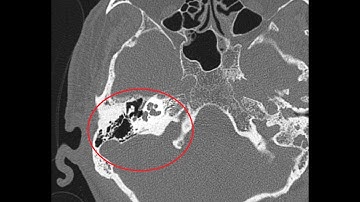

CT Temporal Bone Made Easy (Part 1) - Step by Step Approach